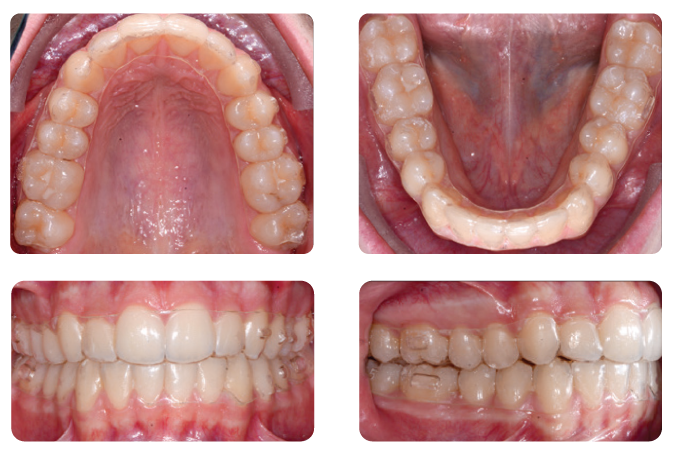

Below picture before treatment.

Clear aligner therapy has been shown to be effective in resolving mild to moderate malocclusions, with shorter treatment and less chairtime compared to conventional systems¹. To overcome some of the aligners’ biomechanical limitations while still enabling aesthetic treatment of more complex clinical conditions, clear aligners can be combined with various types of auxiliaries [2-4]. Let’s look at the case of an 14-year-old male patient with Class II relationship on right and edge-to-edge relationship on left before treatment.